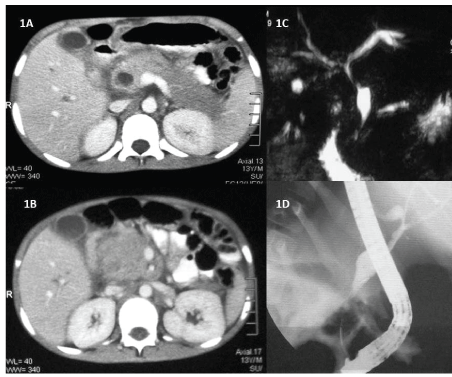

图1:(1A) CECT显示扩张的肝内胆管根和扩张的CBD,壁增厚;

(1B) CECT显示胰腺头体积大;

(1C) MRCP图像显示CBD中下部扩张,近下部狭窄;

(1D) ERCP:透视图像显示CBD中下部扩张,近下部狭窄。内窥镜是可见的。

当尝试减少类固醇,AEC从113增加到3500/µL时,患者出现症状,伴有疼痛和黄疸。实验室评价血清淀粉酶480 U/L(正常0 ~ 70 U/L),总胆红素:6.5 mg / dL(正常的0 - 1 mg / dL)结合胆红素5 mg / dL(普通0 - 0.3 mg / dL)、天冬氨酸转氨酶53 IU / L(正常厅IU / L),丙氨酸转氨酶95 IU / L(正常2-41 IU / L),碱性磷酸酶480 IU / L(正常42 - 128 IU / L),白蛋白4.1 g / dL(正常3.4 - -4.8 g / dL)、总蛋白7.5 g / dL(正常6.4 - -8.3 g / dL),凝血酶原时间9.8 s(正常9.0-11.5 s),国际标准化比值1.0,活化部分凝血酶时间26 s(正常22-34 s)。ct增强显示肝内胆管扩张,胆总管扩张,胆总管壁增厚(图1A)。胰头体积大(图1B)。磁共振胰胆管造影(MRCP)显示CBD中下部扩张,近下部狭窄(图1C)。为了缓解梗阻,行内镜逆行胰胆管造影(ERCP),显示十二指肠黏膜浸润,并证实MRCP的发现(图1D)。胆道减压采用7法国胆道双猪尾支架置入,减轻了黄疸。ERCP从远端CBD进行刷检,细胞学检查显示除胆管细胞外还有嗜酸性浸润。 The steroids were escalated to 2 mg/kg with reduction in AEC to 195/µL. The child was doing well on follow-up but unfortunately while returning to home after follow-up consultation he met road-side traffic accident and died on spot.